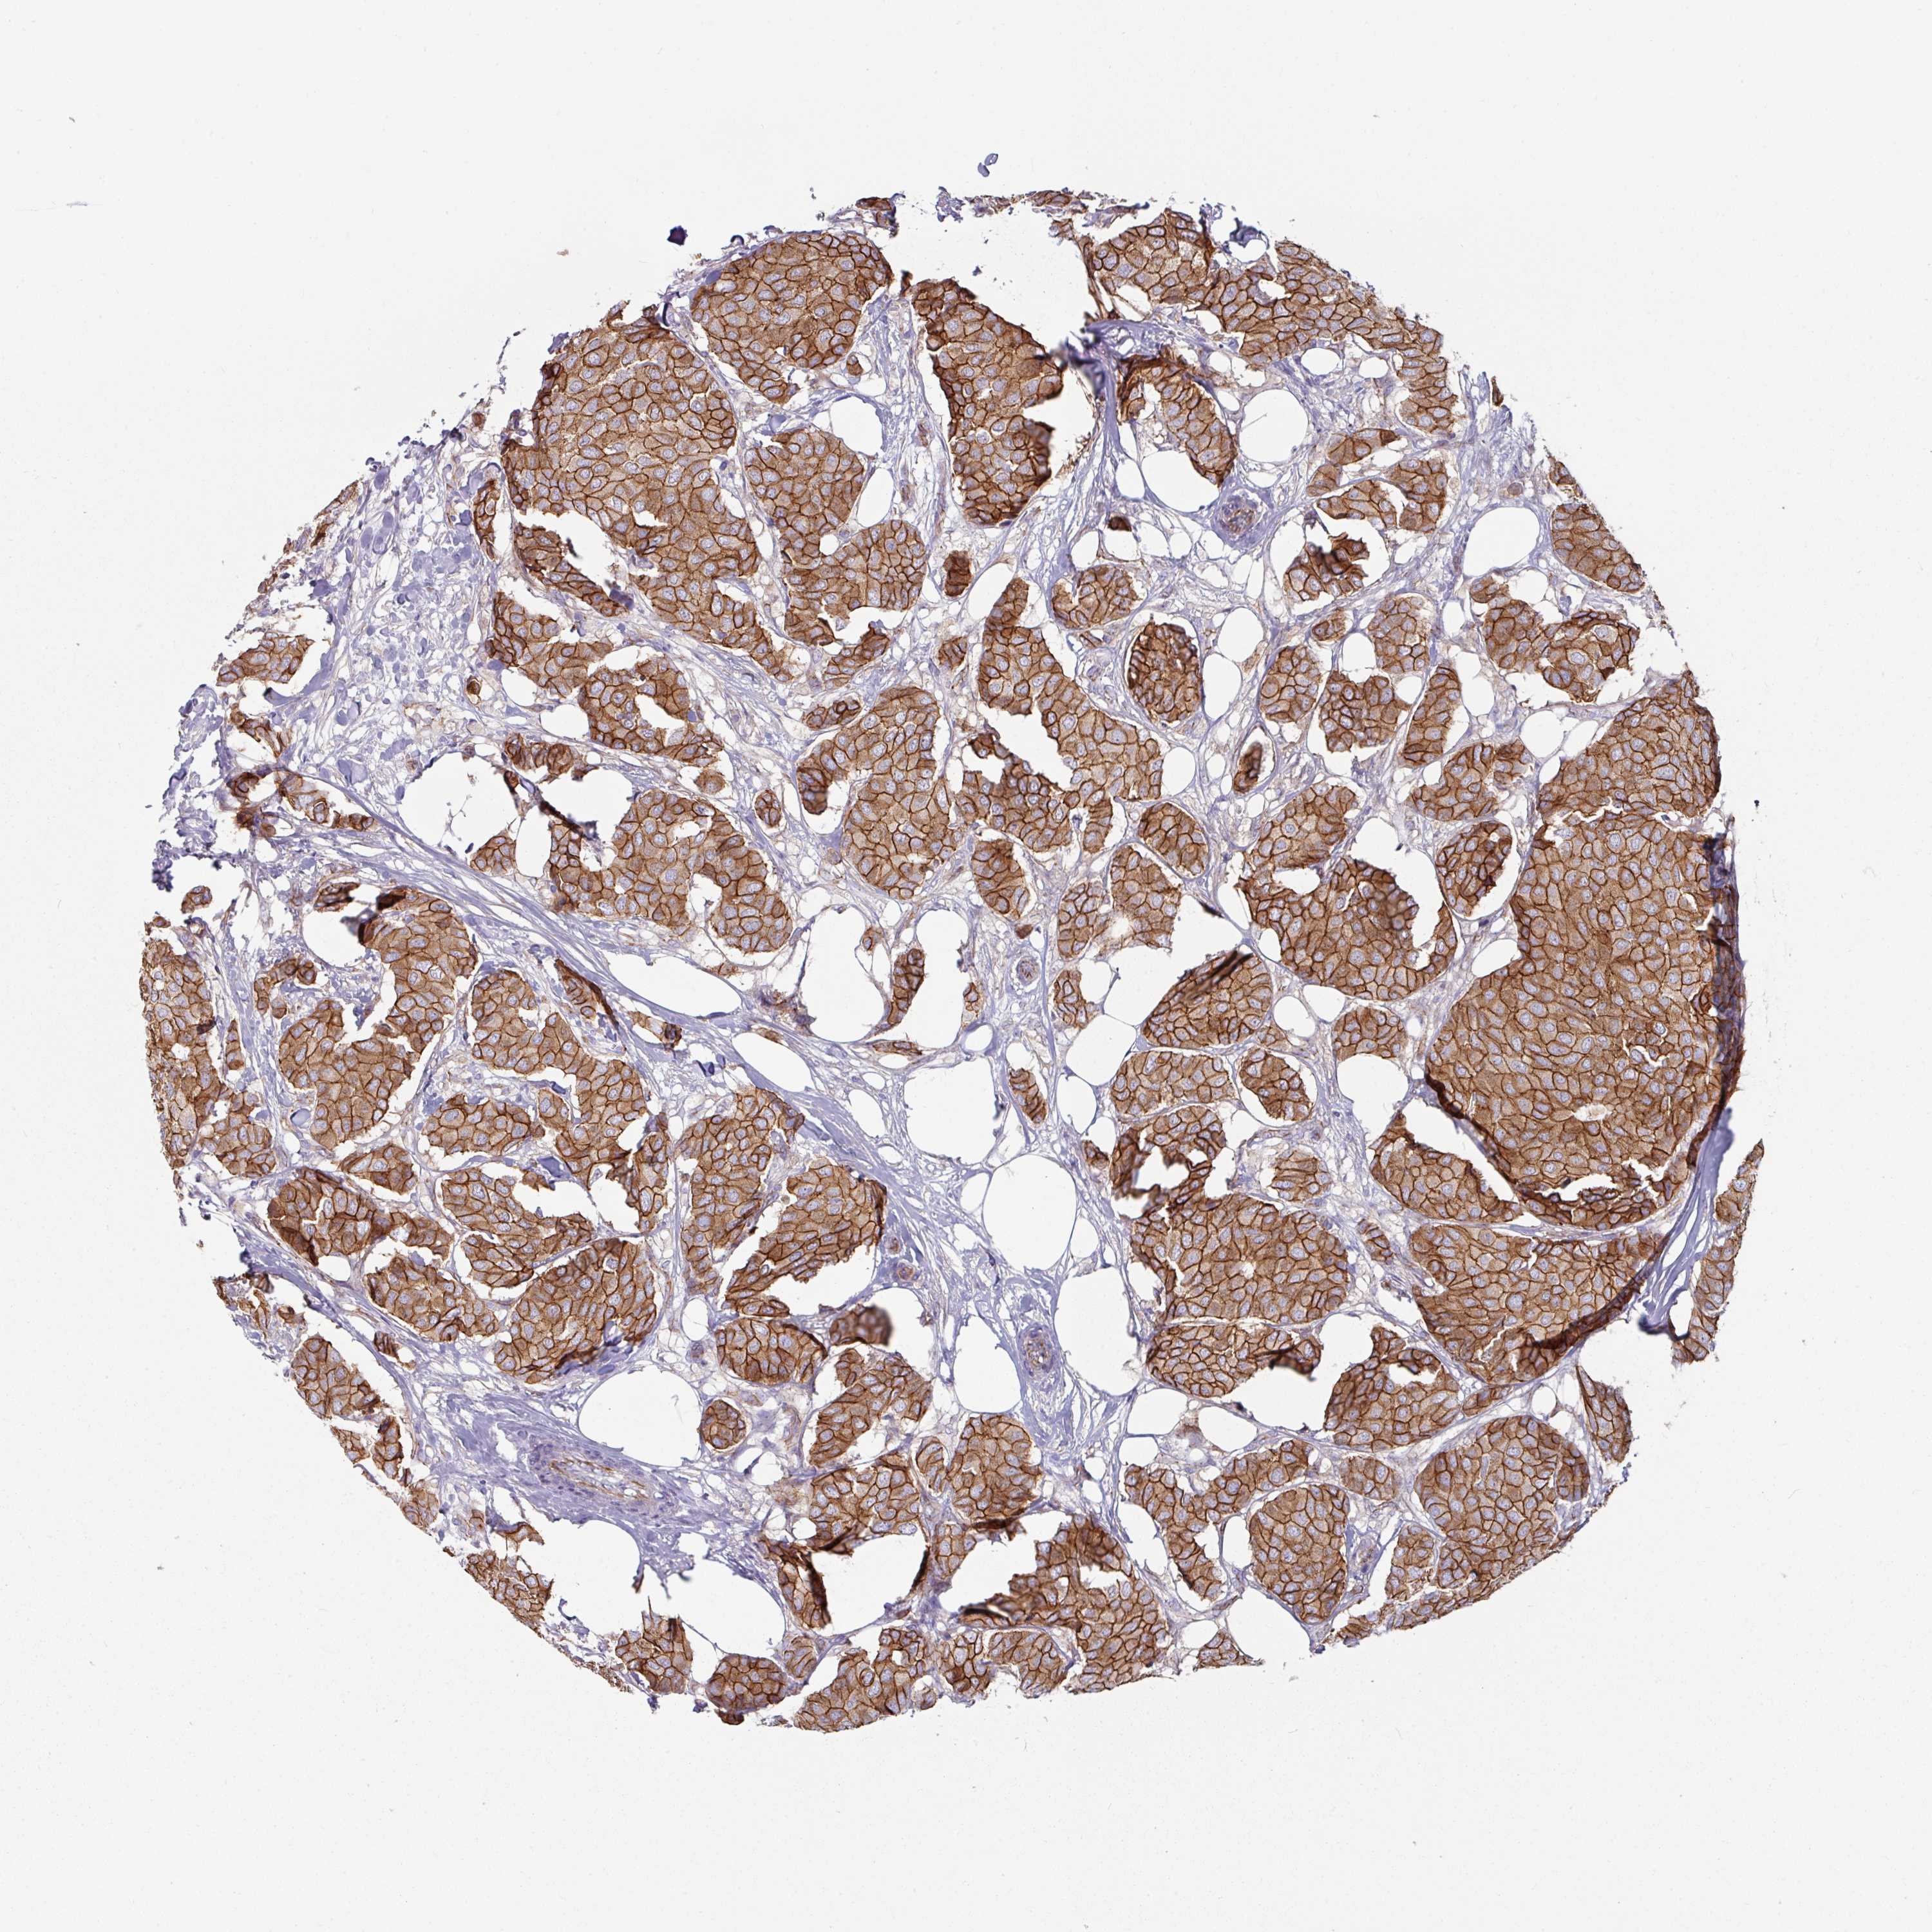

CANCER BREAST CANCER Show tissue menu

BRCA TCGA BRCA VALIDATION PROTEIN EXPRESSION